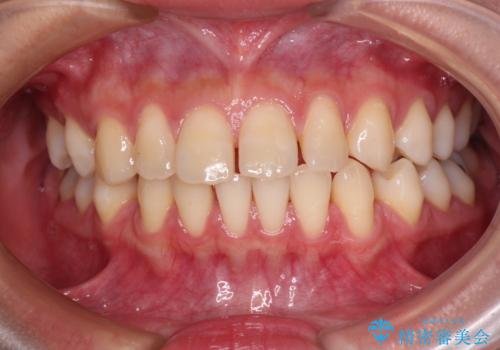

[ 歯を抜かないマウスピース矯正 ] 不揃いの目立つ前歯をきれいにしたい

担当医 大元洋佑